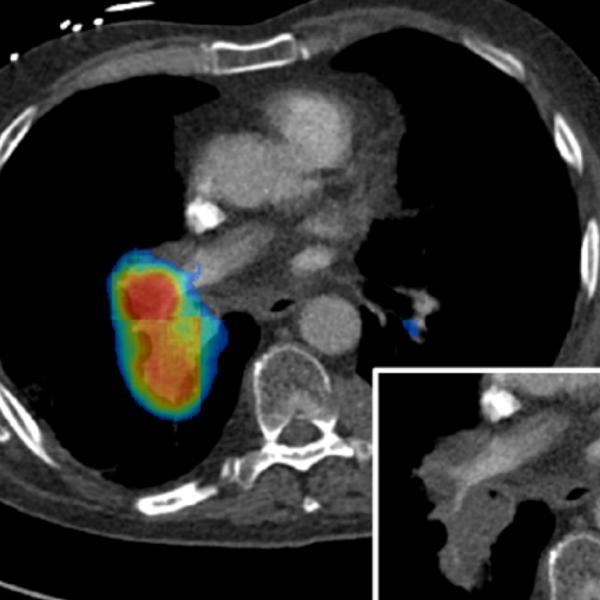

I work at the intersection of artificial intelligence, computational science, and clinical medicine. At Siemens Healthineers in Princeton, NJ, I lead multiple research and product development initiatives utilizing AI/ML and Digital Twin technologies, translating cutting-edge algorithms into FDA-cleared products that improve patient outcomes worldwide.

My work spans the full lifecycle: from foundational research and algorithm development to regulatory clearance and real-world clinical validation. I hold 100+ issued or pending patents and have published extensively in venues including MICCAI, JACC, IEEE TMI, and the Journal of Applied Physiology.